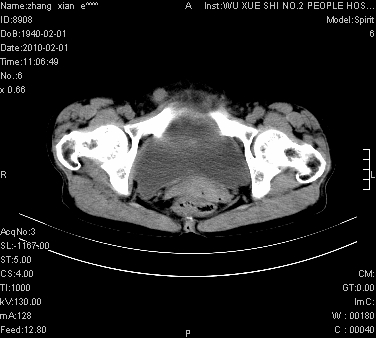

标题: CT24434:70岁 女 腹胀,腹水原因待查 [打印本页]

标题: CT24434:70岁 女 腹胀,腹水原因待查

腹盆腔大量积液,子宫增大,子宫颈增大外形不规则,内见低密度影,膀胱后壁显示不清,右腹股沟肿大淋巴结,脾脏囊性占位,子宫颈占位,子宫颈癌?建议增强。

子宫、宫颈占位?转移性腹水?肝性腹水?脾脏囊性占位,囊肿?血管瘤?淋巴瘤?

腹盆腔大量积液,子宫增大,子宫颈增大外形不规则,内见低密度影,膀胱后壁显示不清,右腹股沟肿大淋巴结,脾脏囊性占位,子宫颈占位,子宫颈癌?建议增强。支持!